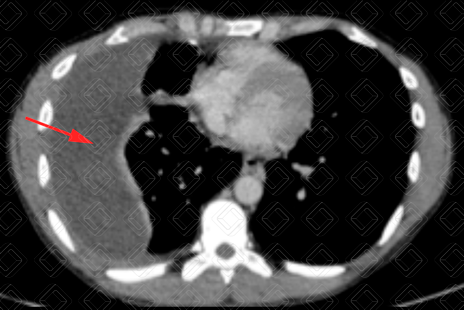

Descrição das figuras 4 e 5: Tomografia computadorizada do tórax evidenciando pequeno derrame pleural bilateral (setas vermelhas), com densidade líquida, ao redor de 2 UH.

• Tomografia computadorizada (TC) do tórax : Em geral, é usado somente nos casos mais graves, como suspeitas de neoplasia, complicação de derrame parapneumônico ou quando a causa do derrame pleural permanece desconhecida. Em geral, a densidade do derrame pleural na TC encontra-se entre 10-20 UH (densidade líquida). Figuras 1 e 2;